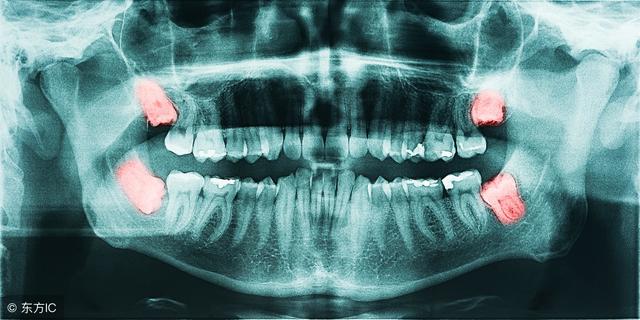

智齿就是口腔中的最后面的臼齿,有人会长,有人终生都不会长。不少人体验过智齿犯了,会疼的要命。

1. 影响正常咬合。阻生智齿的生长位置是不足的,也没有对应对颌牙齿,使之不能建立正常的咬合关系,长时间就会导致张口疼痛、磨牙等症状,对青壮年的身心影响较大。

2. 冠周炎反复发生。阻生的智齿的周围软组织和牙齿之间会形成一盲袋(盲袋就是不宜清洁到的一盲行区域)就容易形成食物、细菌的堆积,当抵抗力下降就会出现冠周炎。

3. 造成龋齿。智齿的生长导致食物、细菌的堆积繁殖,病菌就会侵入人体造成龋齿形成。

4. 邻牙拥挤和松动。由于智齿的长歪没有足够的空间生长,就会挤压到相邻的牙齿,使相邻的牙齿松动,产生牙痛出血等症状。